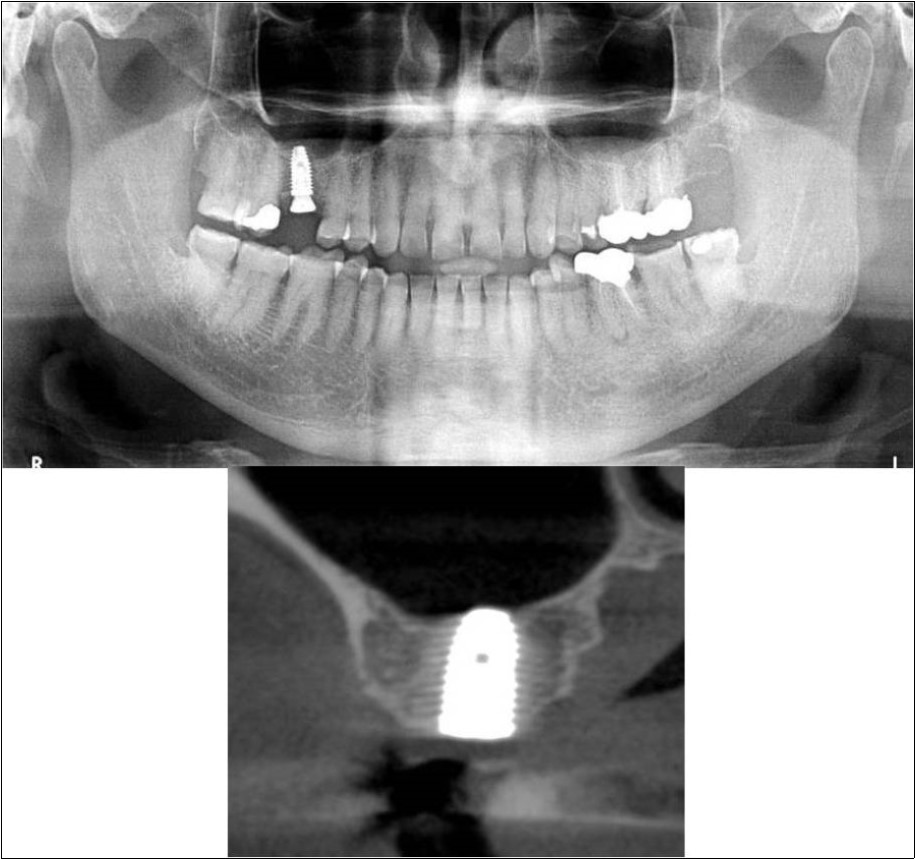

Clinical and Radiological Assessment:

1.Partially edentulous maxillary arch with missing 16;

2.Increased pneumatisation of right maxillary sinus;

3.Height of available bone- 5.3mm;

4.Transverse thickness of available bone (CBCT evaluation)- 10.2mm;

5.Inter-ridge space adequate to place implant (10mm).

Treatment:

Patient underwent the procedure of indirect sinus elevation using sinus osteotomes in relation to 16 region. Calcium phosphosilicate putty was dispensed as the graft material through the crestal osteotomy site to maintain the elevated sinus membrane followed by placement of a dental implant measuring 5 x 10mm under local anaesthesia and strict aseptic protocols. The implant was allowed to osseo-integrate for a period of six months during which the patient was followed-up periodically and was assessed for peri-implantitis, crestal bone loss and mobility. At the end of 6 months, a repeat CBCT scan was advised to evaluate the increase in bone height. (Figure 11a,b, pre-treatment; Figure 12a,b, post-treatment)

Figure 11.(a,b) Pre-treatment OPG and cross section of CBCT showing residual alveolar bone height for Case No.3

Figure 12.(a,b) Post-treatment OPG and cross section of CBCT showing residual alveolar bone height for Case No.3;